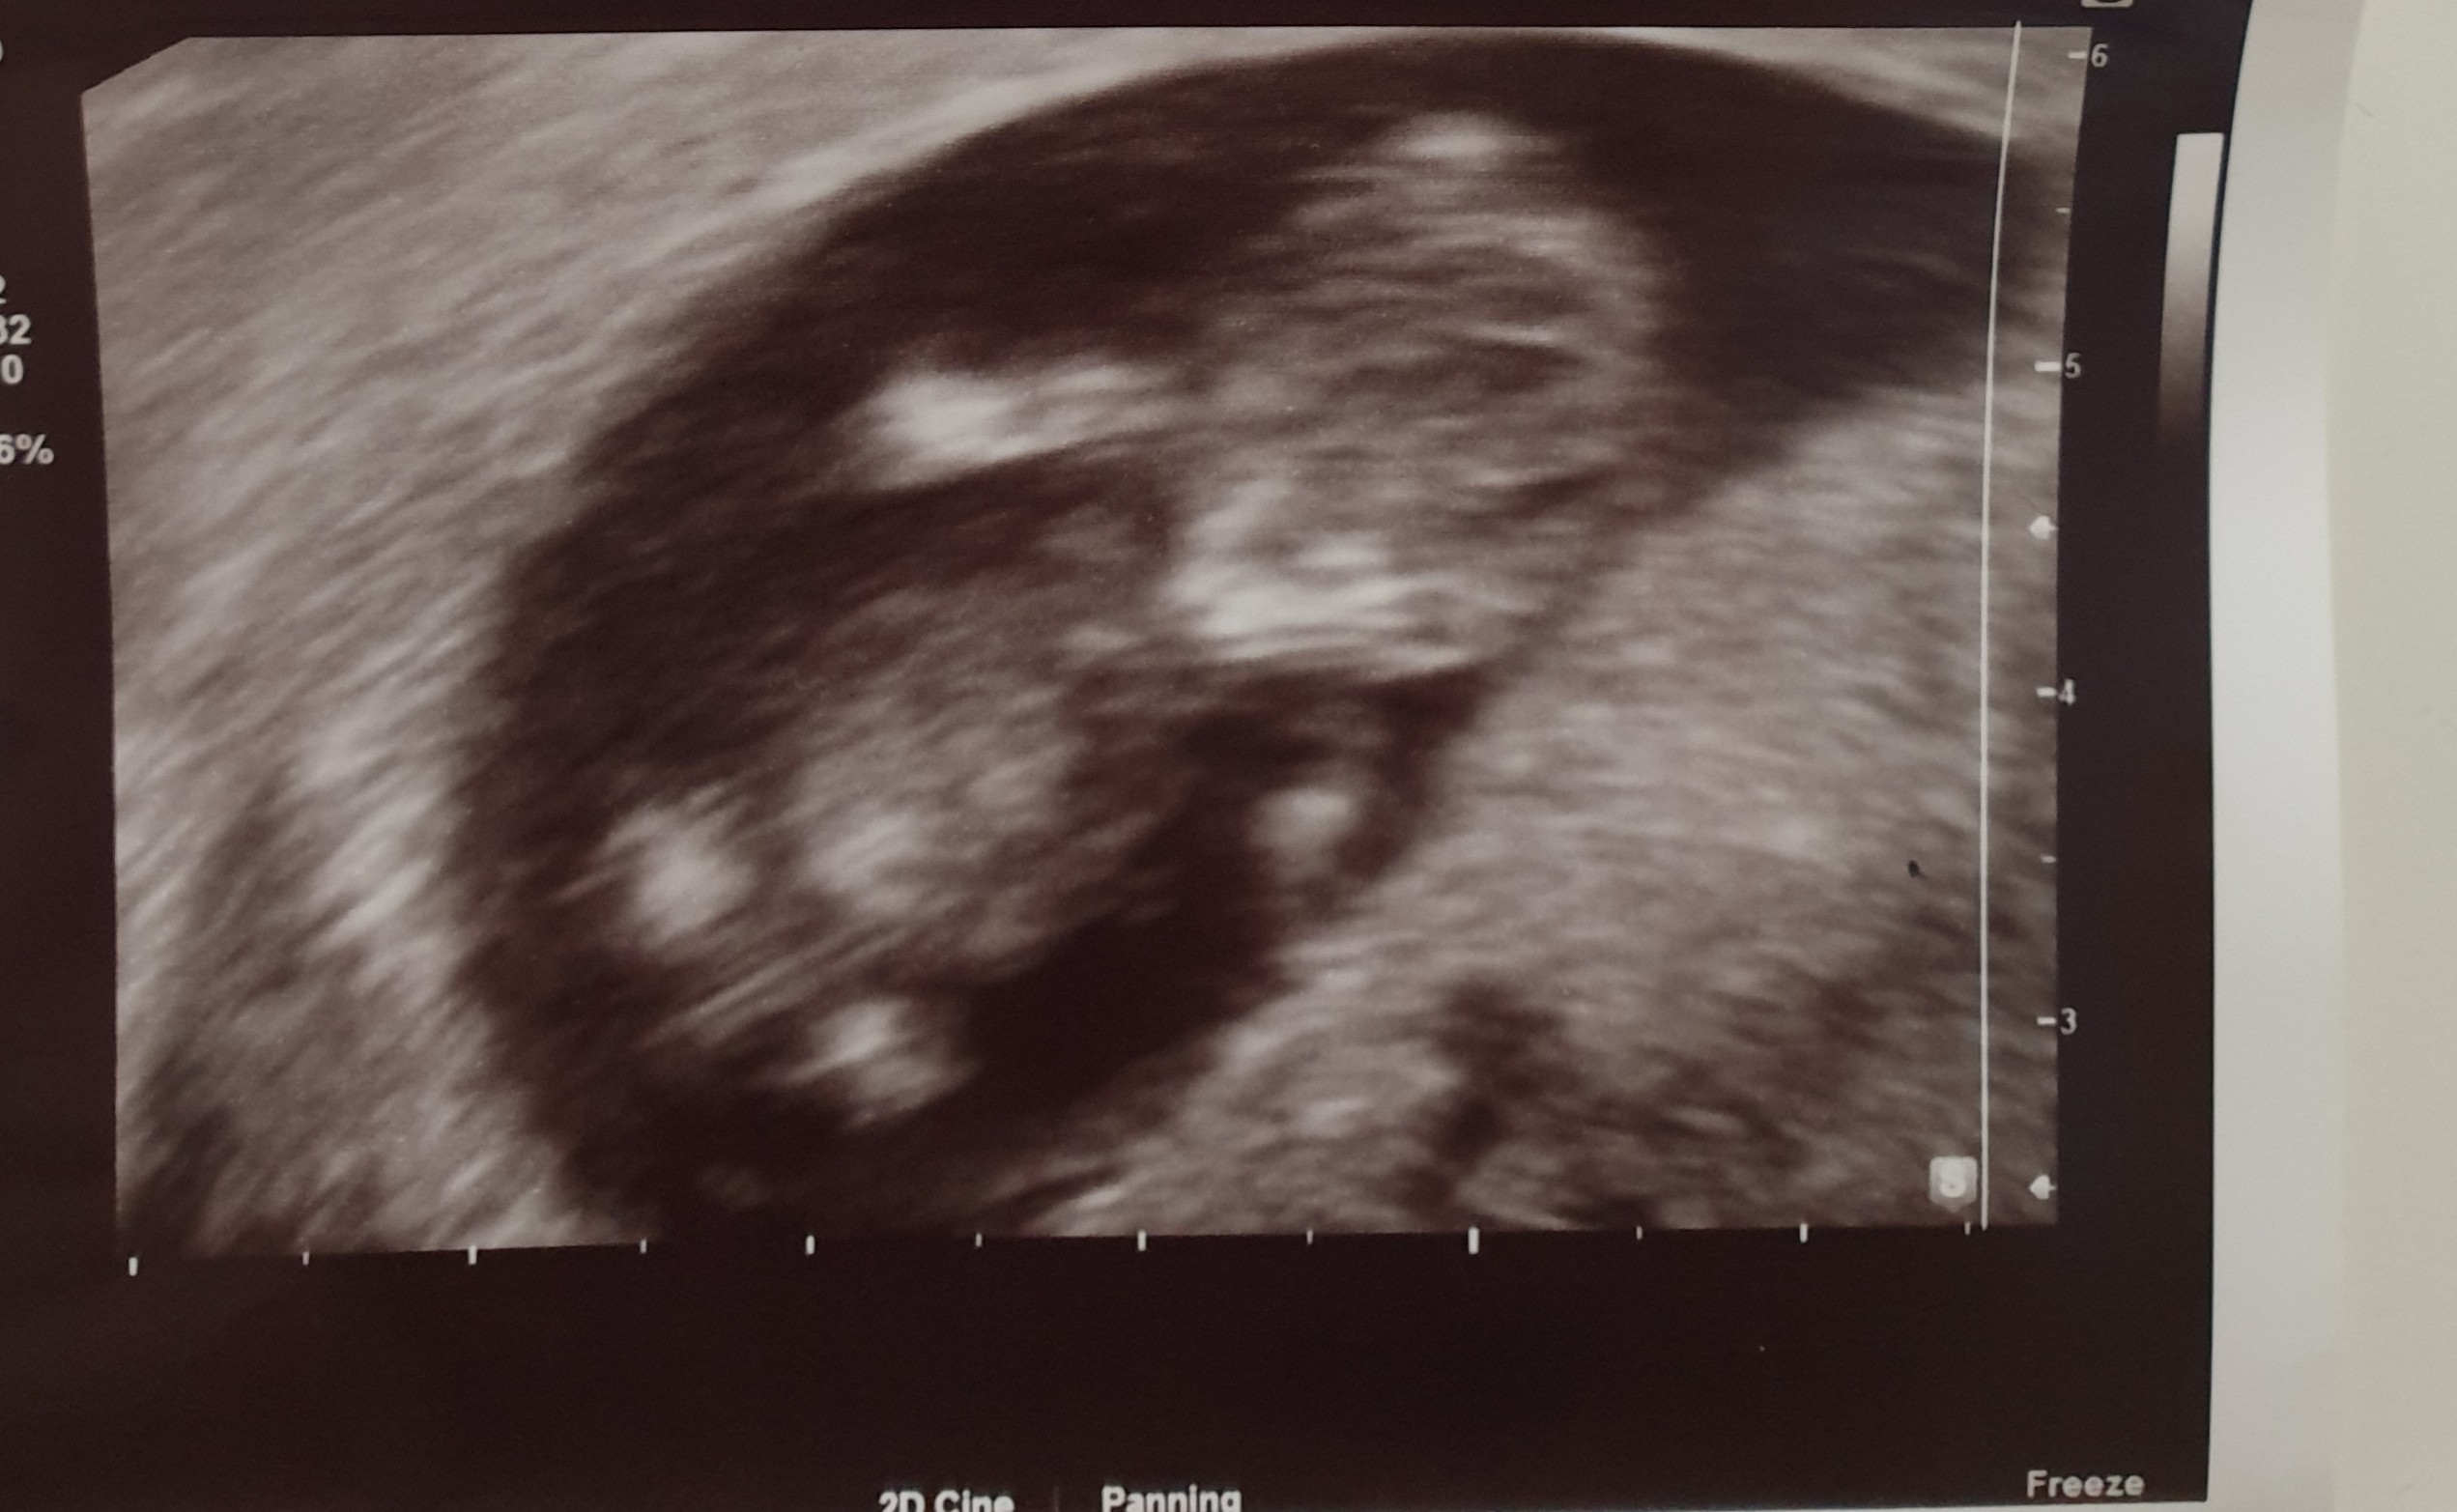

Jestem po wizycie. Wszystko w najlepszym porządku. Na 80% będę dziewczynką 😉

Załączniki

• 20200316_165602.jpg

20200316_165602.jpg

457,8 KB · Wyświetleń: 146